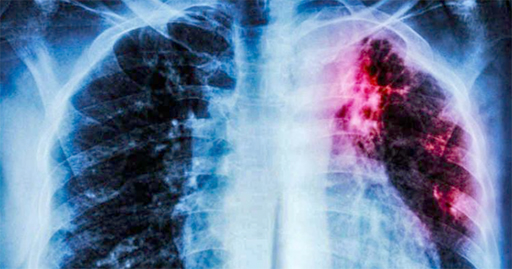

Para entender más esta patología hay que saber que la tuberculosis (TBC) es una enfermedad infectocontagiosa crónica producida por el bacilo de Koch, que se localiza generalmente en el pulmón, aunque puede afectar otros órganos.

Existen dos tipos de tuberculosis: pulmonar, que es la más frecuente y representa alrededor del 80 al 85% del total de los casos, y la extrapulmonar, que afecta a otros órganos del pulmón como la pleura, ganglios, aparato genitourinario, columna, entre otros.

En el primer caso, la persona presenta signos respiratorios como tos seca o productiva, expectoración con o sin hemoptisis, dolor torácico y síntomas generales como anorexia, astenia, adinamia, sudoración nocturna, pérdida de peso y a veces fiebre prolongada. Para evitar la propagación del mismo, el paciente debe comenzar el tratamiento específico.